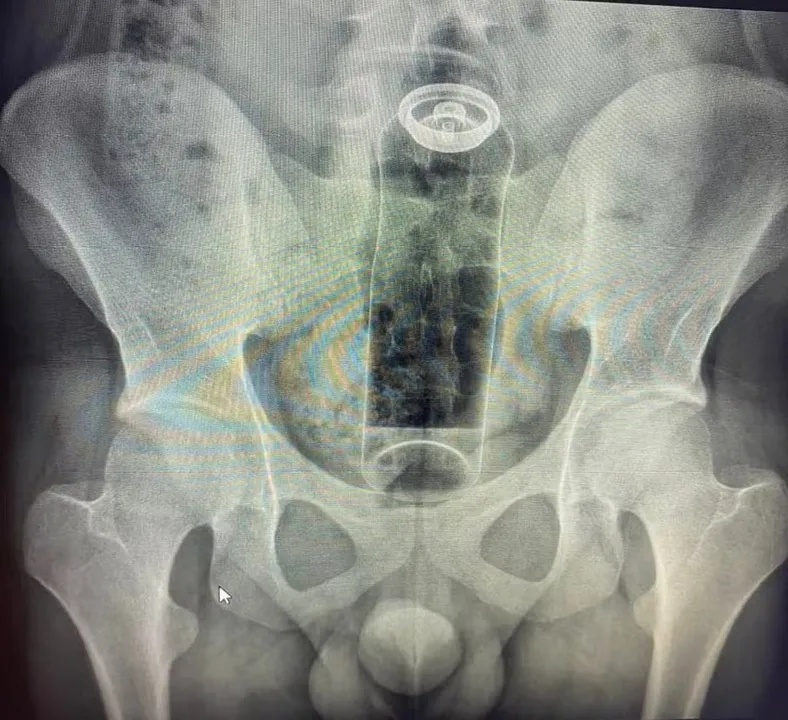

Jovem é internado com desodorante preso no reto

Um jovem de 19 anos foi internado, após ficar com um desodorante preso no reto durante uma prática sexual. Não há informações sobre onde o caso ocorreu, no entanto, o médico Daniel Brosco, cirurgião coloproctologista conhecido nas redes sociais, detalhou a situação.

O paciente teria introduzido o objeto no ânus, porém, a embalagem acabou subindo e ele não conseguiu fazer a retirada em casa, necessitando de auxílio médico.